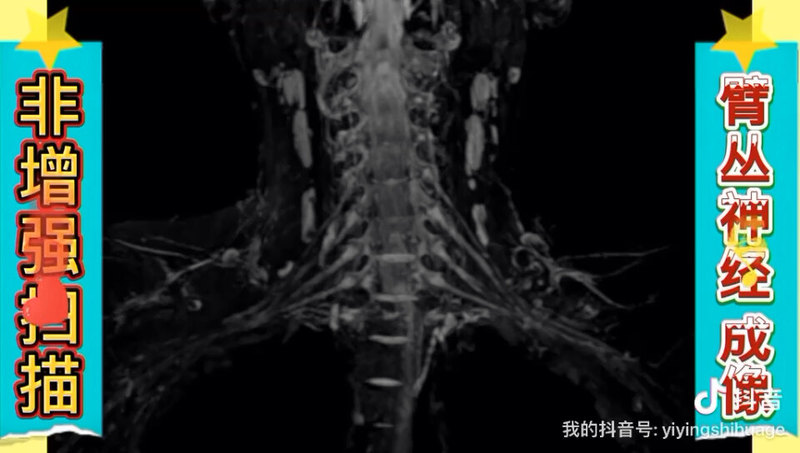

做完頭顱CT后仍需進行顱腦磁共振(MRI)檢查,主要因為兩種檢查方法在成像原理、適用場景和疾病檢出能力上存在互補性,具體原因如下:1.CT與MRI的成像優(yōu)勢不同CT通過X射線快速掃描,對急性出血(如腦出血、顱骨骨折)和鈣化病變的檢出率更高,適合急診患者快速篩查。而MRI利用磁場和無線電波成像,對軟組織(如腦腫瘤、腦梗死、腦炎)和后顱窩病變(如小腦、腦干)的分辨率更優(yōu),能發(fā)現(xiàn)CT難以顯示的細微病灶。2.檢查目的的階段性醫(yī)生通常先安排CT檢查以排除緊急情況(如腦出血),若患者癥狀持續(xù)或存在其他異常(如慢性頭痛、神經(jīng)功能損傷),則需進一步通過MRI明確病因。例如,CT可能漏診早期腦梗死或腦白質(zhì)病變,而MRI的彌散加權(quán)成像(DWI)可檢測超急性期腦梗死。3.適應人群與安全性CT存在輻射,不適合孕婦或需多次檢查的患者;MRI無輻射且對軟組織顯像更清晰,但檢查時間較長且禁忌癥較多(如體內(nèi)有金屬植入物)。醫(yī)生會根據(jù)患者具體情況(如年齡、病史、體內(nèi)金屬情況)選擇組合檢查。綜上,CT和MRI是互補而非替代關系。通過聯(lián)合使用兩種檢查,可全面評估腦部結(jié)構(gòu)與功能,提高診斷準確性。